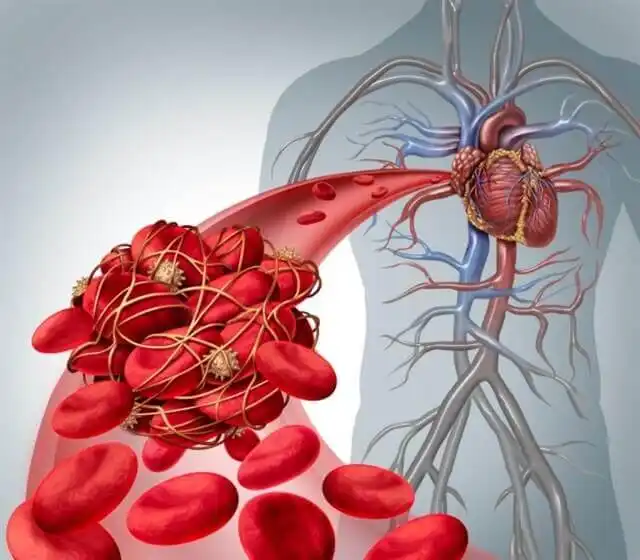

폐 색전증은 덩어리가 폐로 향하는 혈류를 막는 문제다. 가장 일반적인 원인은 혈전이지만, 지방이나 공기 색전증이 발생할 수도 있다.

간단히 말해, 폐 색전증은 폐동맥의 폐색으로 갑자기 발생한다. 일반적으로 정맥 혈전의 일부가 분리되어 혈액을 타고 이동하다가 폐의 동맥에 박히는 것이 원인이다.